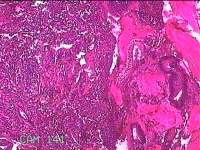

宫腔内容物

性别

女

年龄

48岁

临床诊断

1.异常子宫出血 3.慢性宫颈炎 2.宫颈赘生物性质待查

一般病史

月经量增多16年。

标本名称

大体所见

灰白暗红色不规则碎组织1.5x1.3x0.3cm一堆。

图2